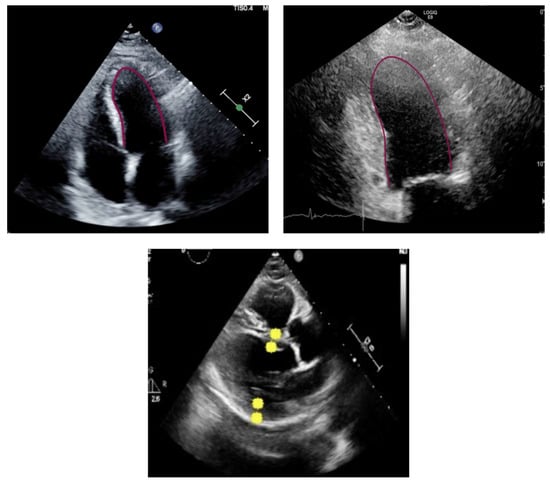

Assessment of an Artificial Intelligence Tool for Estimating Left Ventricular Ejection Fraction in Echocardiograms from Apical and Parasternal Long-Axis Views

2.1. Measurements